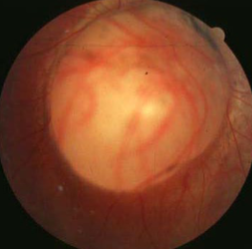

coloboma of ONH

etiology: incomplete closure of embryonic choroidal fissure

rare, unilateral or bilateral

appearance:

inferior portion of ONH affected w/ significant excavation & pigment hyperplasia

white bowl-shaped excavation

depth of excavation varies

larger appearing ONH w/ unusual vascular pattern

associations:

coloboma of choroid/retina, lens, iris

complications:

variable VA: normal to NLP

associated VF defects

strabismus

micro-ophthalmos

RD

NTG confusion

must r/o systemic abnormalities